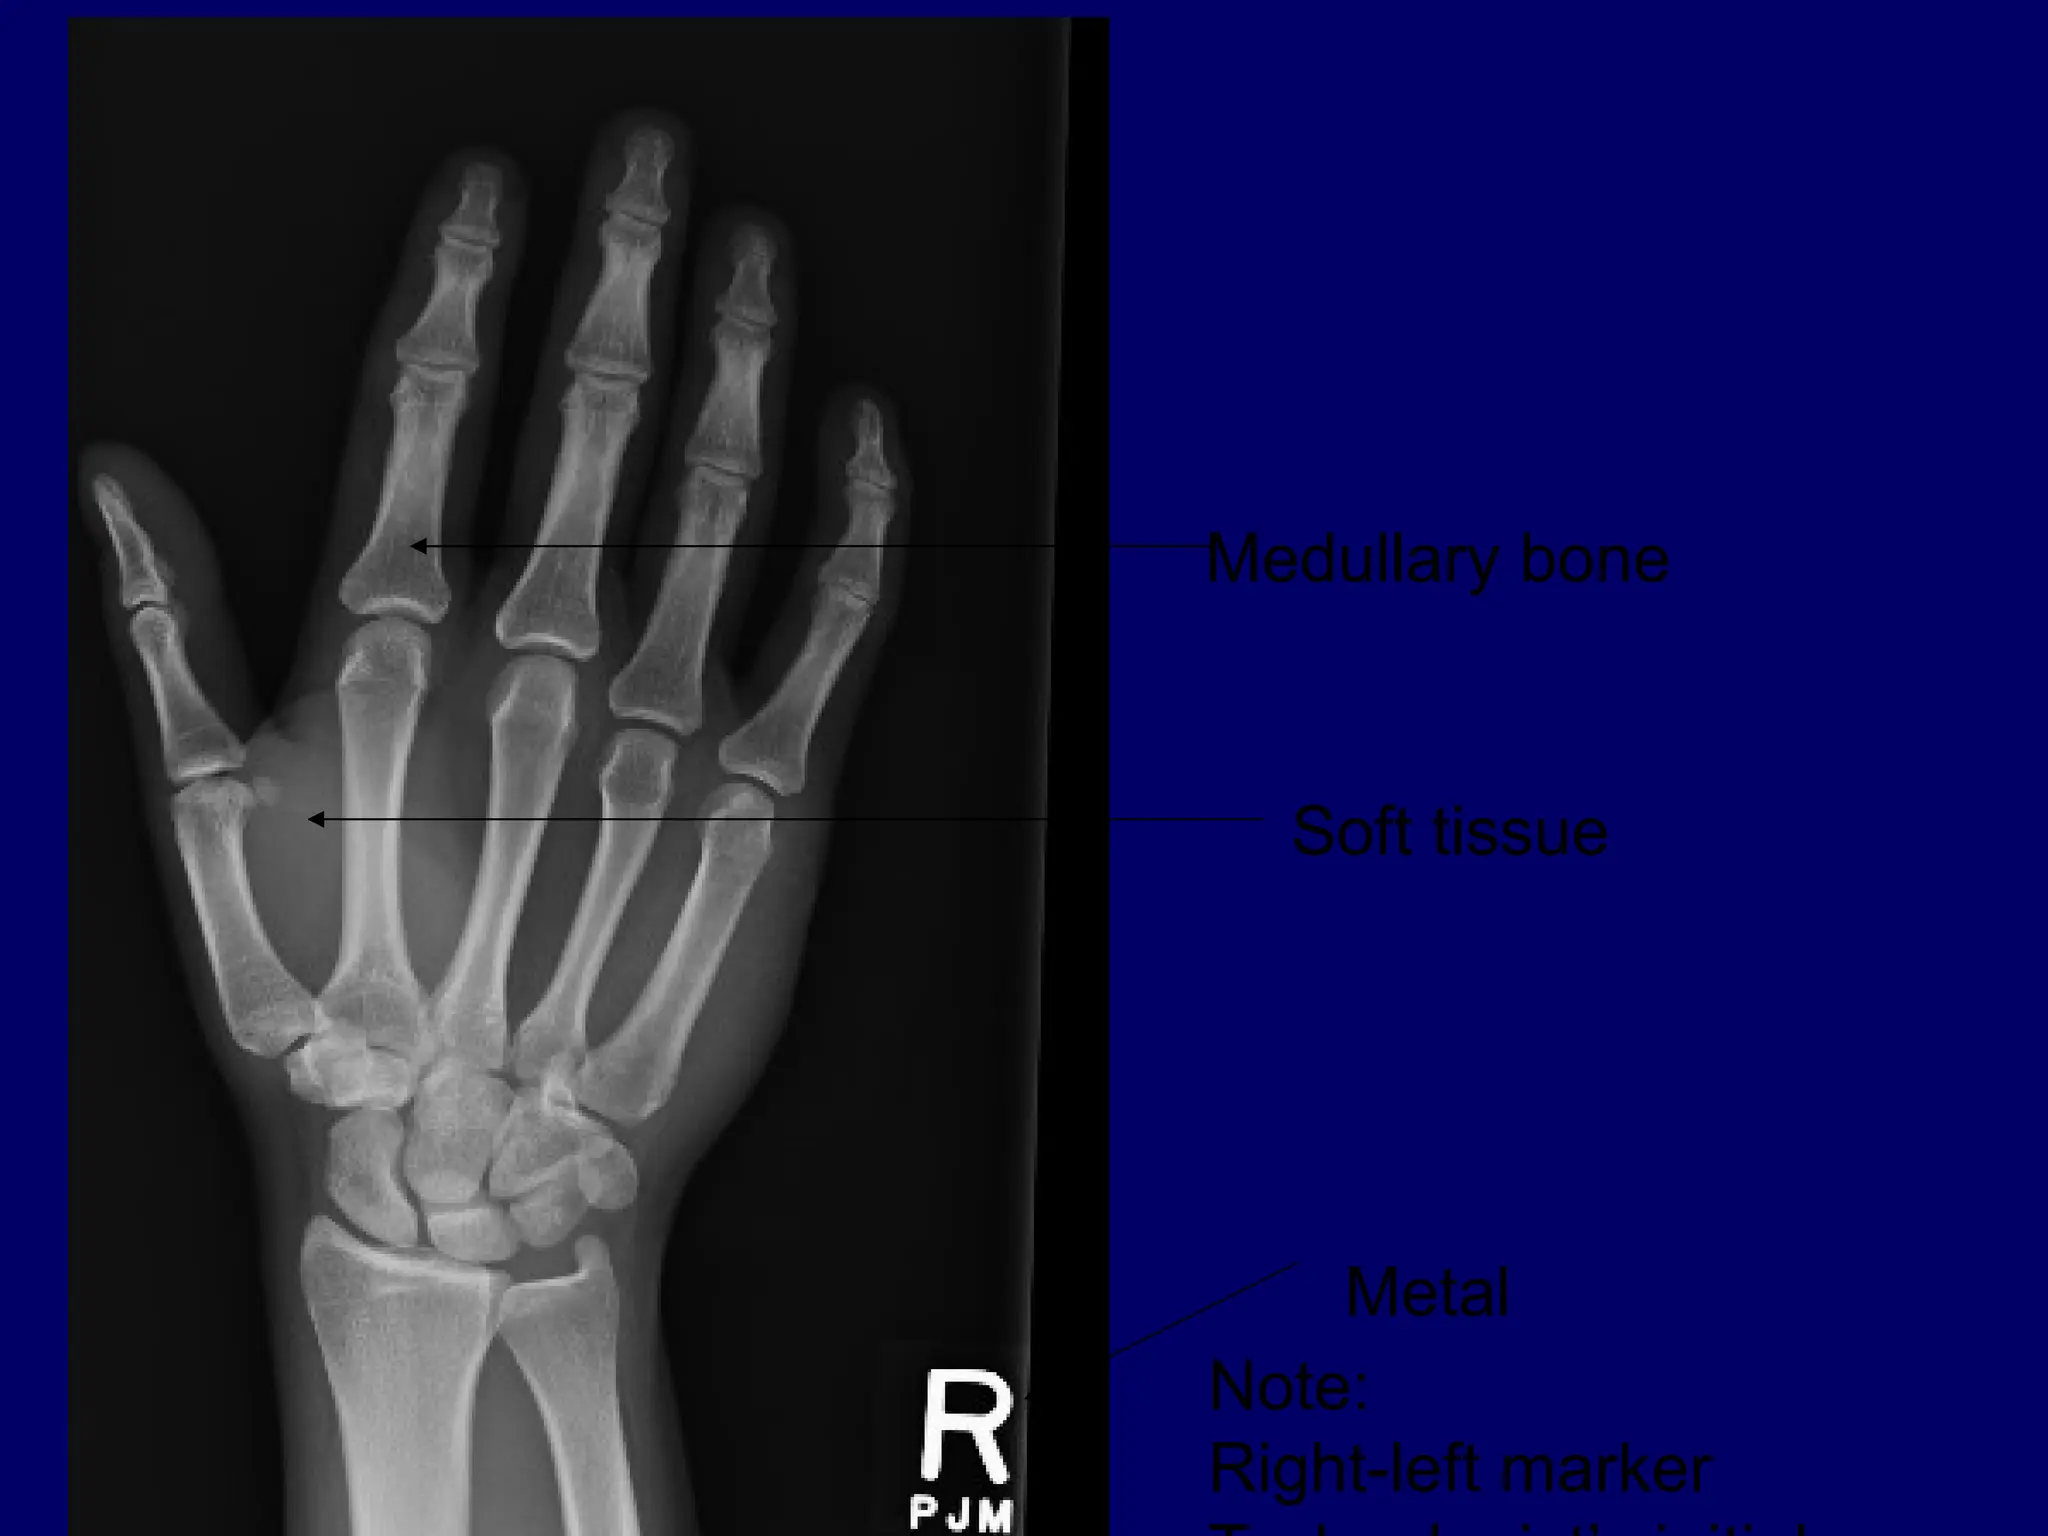

Medullary bone

Soft tissue

Metal

Note:

Right-left marker